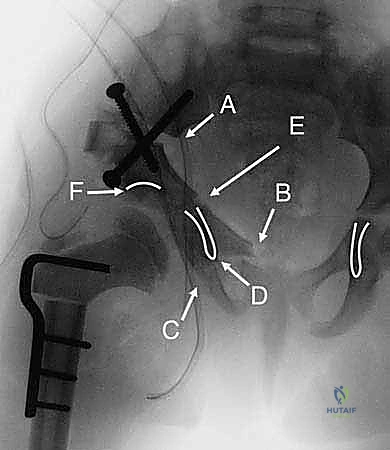

3. مرحلة القطع العظمي (The Three Osteotomies)

هنا تكمن عبقرية الإجراء. يتم استخدام مناشير جراحية دقيقة لعمل قطوع في:

* عظم الإسك (Ischium): العظم السفلي الخلفي للحوض.

* عظم العانة (Pubis): العظم الأمامي للحوض.

* عظم الحرقفة (Ilium): العظم العلوي العريض للحوض.

بمجرد اكتمال هذه القطوع الثلاثة، يصبح التجويف الحقي (الكوب) منفصلاً تماماً عن بقية الحوض، مع بقاء إمداداته الدموية سليمة.

4. إعادة التوجيه والتدوير (Rotation & Redirection)

باستخدام أدوات خاصة، يقوم الدكتور هطيف بتدوير التجويف الحقي الحر في ثلاثة أبعاد (للأمام، وللخارج، وللأسفل) حتى يغطي رأس عظم الفخذ بشكل مثالي وميكانيكي سليم. يتم التحقق من الزاوية الجديدة فوراً داخل غرفة العمليات باستخدام جهاز الأشعة السينية المتحرك (C-arm).

5. التثبيت القوي (Fixation)

بمجرد الوصول إلى الوضع المثالي، يتم تثبيت العظام في مكانها الجديد باستخدام براغي معدنية قوية من التيتانيوم أو دبابيس (K-wires). هذا التثبيت يضمن التحام العظام بشكل صحيح خلال فترة التعافي.